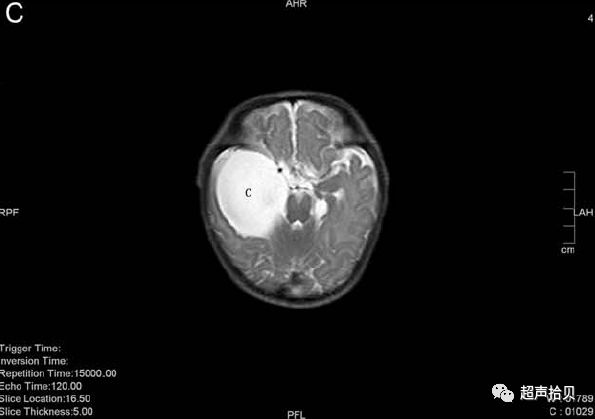

图4:妊娠26周时的产前MRI:第三脑室蛛网膜囊肿的横向(A),矢状(B)和冠状面(C)平面引起脑室扩张

图5:出生后1周进行T1加权轴位MRI扫描。 侧脑室的后角和前角,特别是第三脑室,被蛛网膜囊肿占据。